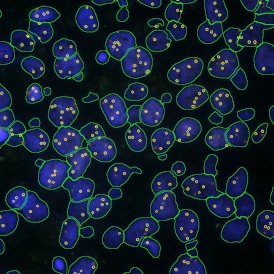

Case Study: Analysis of FISH Using Tissue Cytometry

The IF Dots App in StrataQuest streamlines automated analysis of FISH stainings by detecting nuclei and quantifying dots per cell. This case study shows how the workflow enables accurate, exportable data for genetics research and clinical applications.

Understanding the Different Types of FISH Evaluations

FISH is a powerful imaging-based technique for detecting DNA and RNA sequences directly in cells and tissues. This post explores the advantages of FISH, its complementary methods like CISH and RNAscope, and how TG solutions streamline automated FISH analysis.

How FISH Image Analysis Factors into Next-Gen Digital Pathology

How does FISH image analysis advance digital pathology? Learn how whole-slide imaging and AI-powered algorithms enable fast, accurate detection of chromosomal abnormalities, streamline workflows, and open new possibilities for precision medicine.

Quantitative Image-based Cytometry: Focus on the Foci!

Prof. Nicolas C. Hoch, University of Sao Paulo, is presenting his research on signaling and repair of DNA damage. He and his group are utilizing the power of TissueFAXS i PLUS slide scanning and the high-end image analysis solution, StrataQuest, for their research.